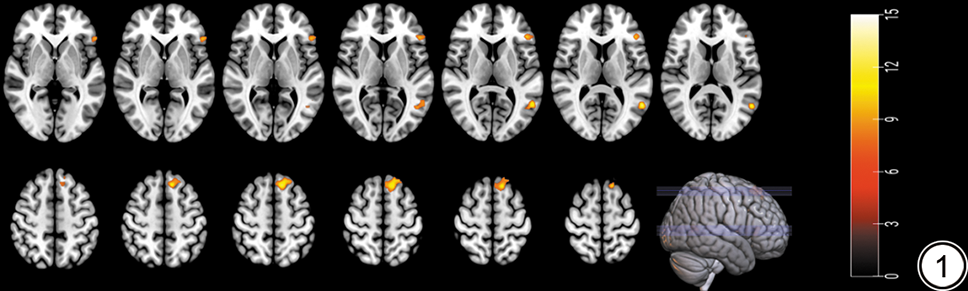

T2DM、PreDM、NGT三组间全脑灰质体积差异有统计学意义的脑区:左侧三角部额下回、左侧颞中回、左侧内侧额上回。事后分析结果显示:与NGT组对比,T2DM组左侧颞中回、左侧内侧额上回的灰质体积减小,PreDM组左侧三角部额下回的灰质体积减小;与PreDM组对比,T2DM组左侧三角部额下回的灰质体积增大。结果详见表2图1

图1  T2DM组、PreDM组和NGT组灰质体积差异有统计学意义的脑区。右侧色带条颜色越亮代表统计值F值越大。T2DM:2型糖尿病;PreDM:糖尿病前期;NGT:糖耐量正常。

Fig. 1  Brain regions with statistically significant gray matter volume differences in the T2DM, PreDM, and NGT groups. The brighter the color of the ribbon on the right, the greater the F value. T2DM: type 2 diabetes mellitus; PreDM: prediabetes mellitus; NGT: normal glucose tolerance.